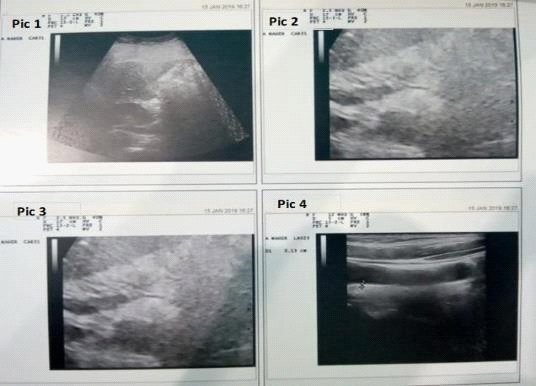

Figure 1: Shows fatty liver grade1, (2) Shows fatty pancreas grade 3, (3) Shows fatty pancreas grade 2 and Pic. (4) Shows CIT >1.1cm.